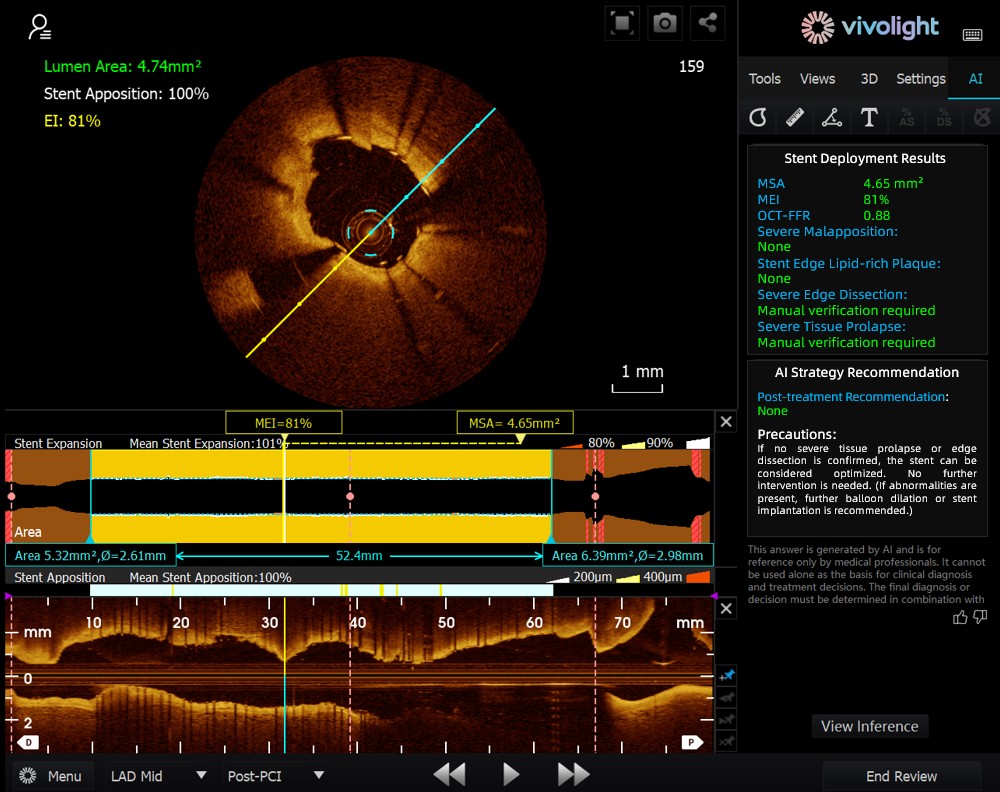

Desarrollado a partir del sistema OCT de Vivolight Medical, el AI-OCT es un sistema inteligente de apoyo a la decisión de última generación para imágenes intravasculares. Integra datos diagnósticos de imágenes intravasculares dispersos —como el diámetro luminal, las lesiones causantes, la OCT-FFR y las características de la placa— en estrategias de tratamiento integrales y recomendaciones prácticas. Como software de investigación independiente integrado en la plataforma OCT, se desarrolla en colaboración con diversos hospitales para crear versiones personalizadas que se adapten a necesidades clínicas específicas.

Durante el foro de vanguardia, los expertos destacaron que el sistema AI-OCT representa un cambio transformador, pasando de la mera visualización de imágenes a la elaboración de planes de tratamiento, lo que permite abordar los desafíos de la sobrecarga de información y la compleja toma de decisiones en los procedimientos de intervención cardíaca, que tradicionalmente dependen en gran medida de la experiencia del médico. Entre las principales ventajas del sistema se incluyen:

●Guía intraoperatoria en tiempo real: Organiza de forma dinámica la información diagnóstica durante la cirugía, proporcionando métricas clave y recomendaciones clínicas.

●Toma de decisiones basada en la evidencia: Todas las sugerencias se ajustan al consenso de expertos y a las guías clínicas, lo que garantiza rigor y fiabilidad.

El sistema AI-OCT adopta una arquitectura de "modelo pequeño + macrodatos + modelo grande": los modelos pequeños permiten una interpretación precisa de las imágenes, mientras que los modelos grandes impulsan un razonamiento clínico integral. Gracias a bases de datos cardiovasculares de alta calidad y a la tecnología de Generación Aumentada por Recuperación (RAG), ofrece soporte integral, desde la evaluación de lesiones hasta el desarrollo de estrategias de tratamiento.